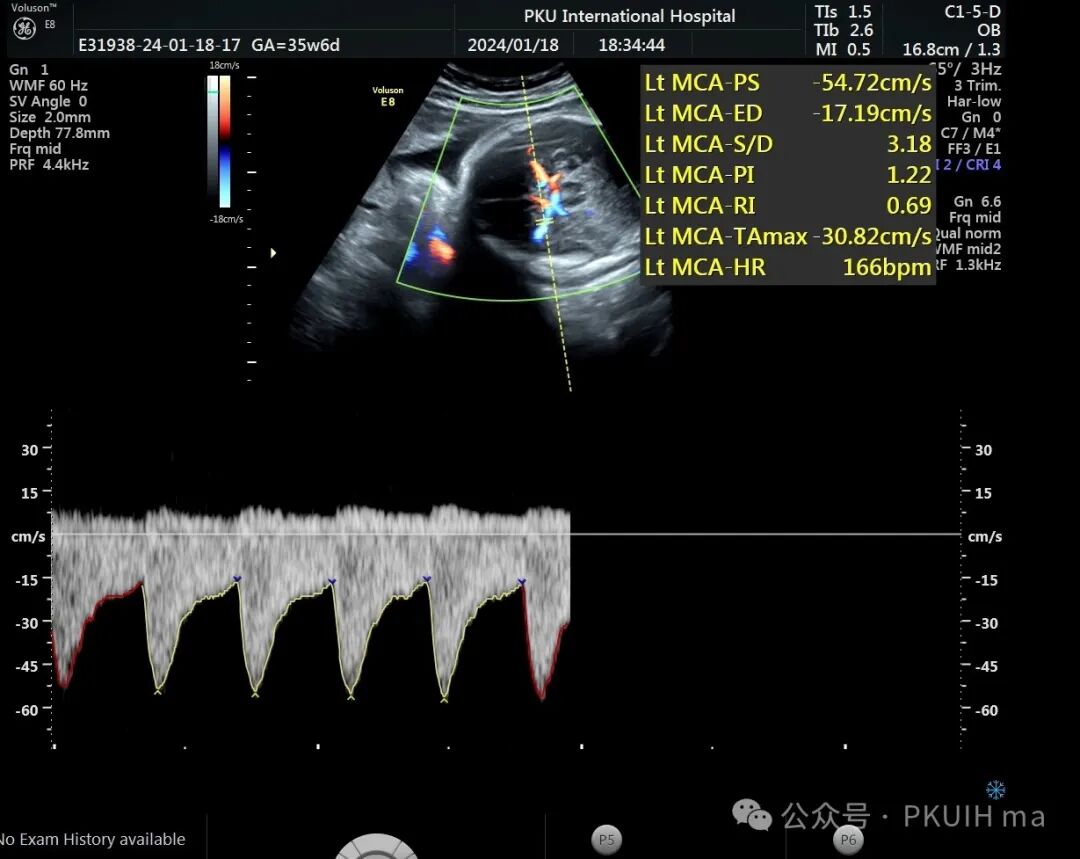

前两天碰到一孕妇胎动减少来诊,孕妇自述下午两点开始发现胎儿无明显胎动,吃了甜的食物和改变姿势还是不怎么动,随于下午六点左右来诊。超声发现胎儿绕颈两周以上且绕的较紧,检查中发现胎儿心率快,胎儿无明显胎动,绕颈处脐动脉血流加速时间延长,胎儿大脑中动脉阻力低,反复测量两侧大脑中动脉阻力均低。胎心监护也不好,随后产科采取紧急剖宫产。

反复测量左右两侧大脑中动脉阻力均低于第五百分位,考虑胎儿存在缺氧